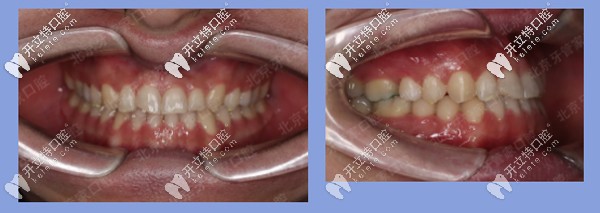

被矯治者基本信息:王先生,22歲,地包天,牙列散縫。

患者牙齒矯正前

前期檢查:反合(又稱地包天),骨性三類,磨牙關(guān)系三類。下前牙已經(jīng)發(fā)生舌傾,存在縫隙。

患者牙齒前期檢查

治療方案:內(nèi)收下牙列,上頜唇傾前牙,代償性掩飾治療。

矯治器:金屬固定矯正

患者地包天牙齒矯正中

矯正時長:23個月

矯正結(jié)果:上下前牙反合解除,上唇突度恢復(fù)豐滿,患者非常滿意。

患者地包天矯正后